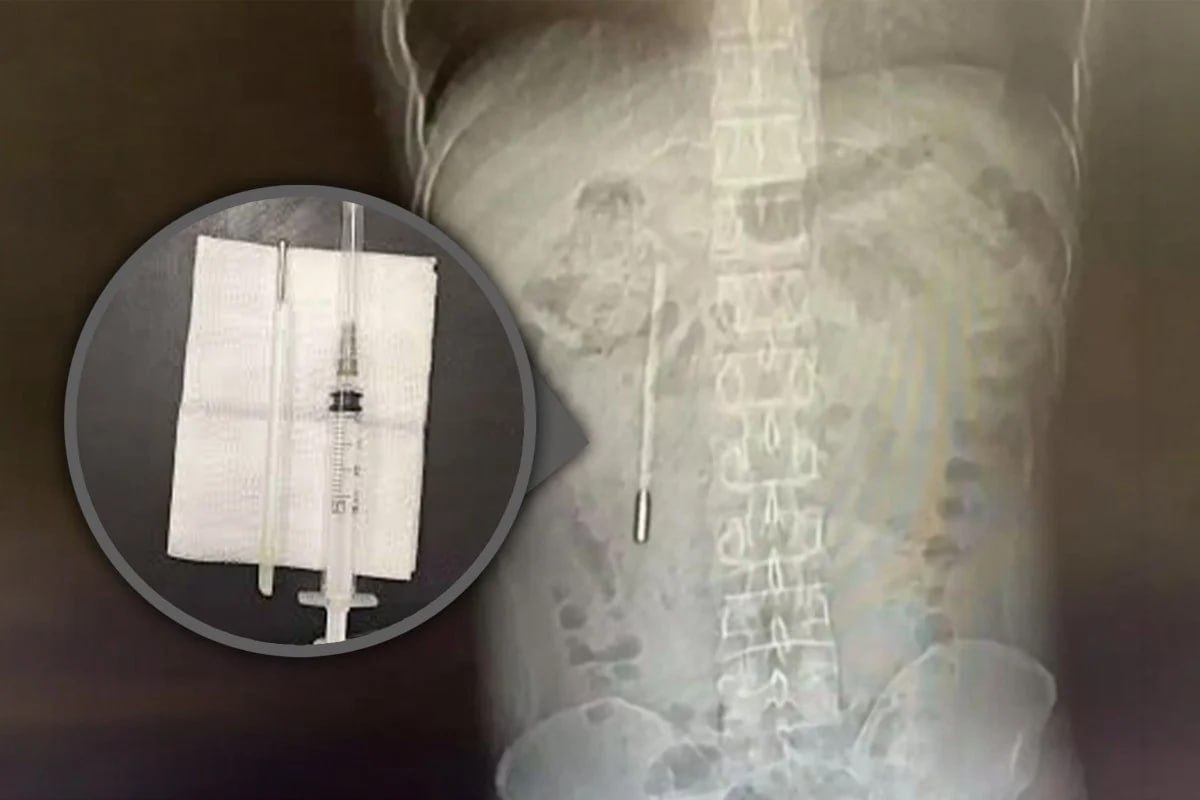

Ένας 32χρονος άνδρας στην Κίνα ζήτησε ιατρική βοήθεια μετά από έντονο πόνο στο στομάχι — και οι γιατροί ανακάλυψαν ένα θερμόμετρο που είχε καταπιεί ως παιδί ήταν ακόμα μέσα του, — South China Morning Post.

Σύμφωνα με αναφορές, κατά λάθος κατάπιε τη συσκευή πριν από χρόνια, αλλά φοβόταν πολύ να το πει στους γονείς του και τελικά την ξέχασε.

Με την πάροδο του χρόνου, άρχισε να πιέζει τους εσωτερικούς ιστούς, δημιουργώντας κίνδυνο εσωτερικής αιμορραγίας.

Οι χειρουργοί αφαίρεσαν με επιτυχία το θερμόμετρο κατά τη διάρκεια μιας επέμβασης.

Η συσκευή παρέμεινε άθικτη, αν και οι ενδείξεις θερμοκρασίας της είχαν ξεθωριάσει.